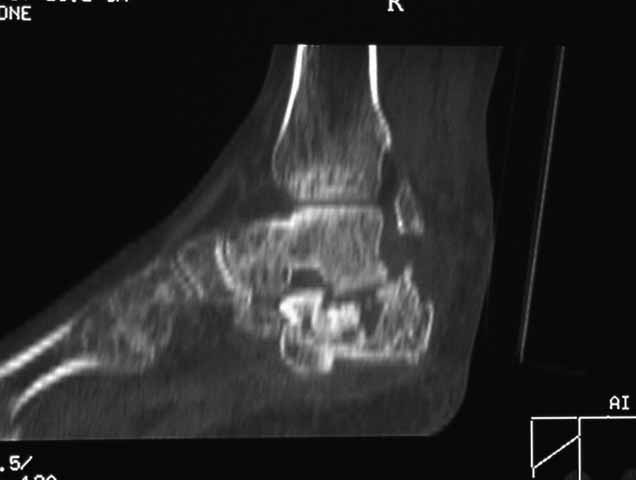

КТ перелома пяточной кости

Пациент 60 лет с производственной травмой-закрытые переломы правой пяточной кости,

тибиального плато слева поступил в феврале с.г. На 4 сутки выполнена открытая репозиция,

остеосинтез внутрисуставного перелома голени, ручная репозиция пяточной кости. Через три

месяца начал ходить с нагрузкой на обе ноги. Консолидация голени с полным восстановлением

функции колена. Правая стопа умеренно отечна, продольно распластана, длительная ходьба

вызывает боли и увеличение отека. Прошел несколько курсов ударно-волновой терапии,

грязелечение, боли и отек уменьшились. В наших планах -оформление на ВТЭК, через год

возможно выполнение подтаранного артродеза.Но после производства КТ в августе появились

сомнения в консолидации перелома.Ранее у нас не было опыта КТ переломов стопы и сканы привели

в замешательство.Прилагаю снимки со дня поступления, августовские пациентом не

представлены.С благодарностью примем советы коллег.